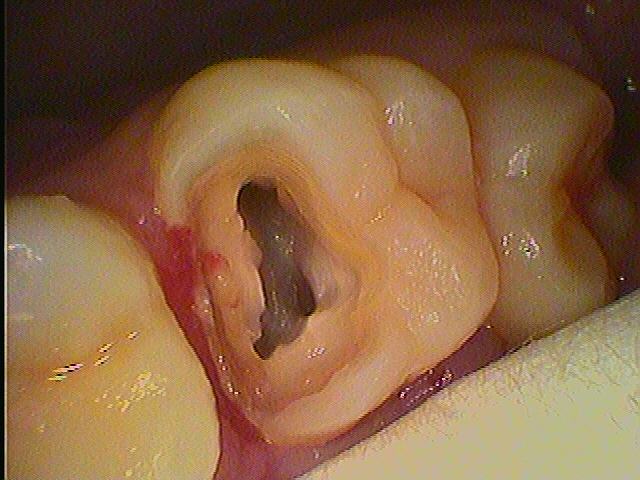

大きな穴が開いていて自発痛が出ています セラミック治療|お知らせ |広島市安佐南区の歯科医院 大きな穴が開いていて自発痛が出ています セラミック治療 トップ お知らせ・ブログ お知らせ 大きな穴が開いていて自発痛が出ています セラミック治療 大きな穴が開いていて自発痛が出ています セラミック治療 大きな穴が開いて最近痛みだしてきたとのこと 中は大穴が開いています 歯髄に達していました 根の治療をしていきました セレックセラミックを入れています きれいな歯に仕上がりました Web診療予約 初めての方へ 選ばれ続ける理由 院内設備について 歯が痛いしみる一般歯科 歯がぐらぐらする歯周病 健康な歯を保ちたい予防歯科 子供の虫歯予防をしたい小児歯科 銀歯をセラミックに審美歯科 白い歯を目指しませんか?ホワイトニング 矯正専門医がいるので安心矯正歯科 抜けた歯を補いたいインプラント・入れ歯 医院案内 スタッフ紹介 メリィハウス歯科クリニックオフィシャルホームページ ラベンダー歯科クリニックオフィシャルホームページ お知らせ・ブログ ホーム 診療科目 一般歯科 歯周病治療 予防治療 小児歯科 審美治療 ホワイトニング 矯正歯科 入れ歯・インプラント マウスピース矯正 初めての方へ 院長・スタッフ 設備紹介 医院案内・アクセス メニューを閉じる